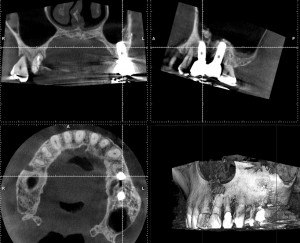

根管治療で現在通院中のNさん。6年前にサイナスリフトを行い2本インプラントを埋入したが順調に経過しているようだ。この時は上顎洞の窓開けを行いたい場所に隔壁があり、これを避けるために2つ小さめの窓を開けて行った。非常にやりずらく苦労した覚えがある。今回は反対側の歯に根尖病変が見つかったので根管治療となった。以前より折れ込んでいたと思われる金属の器具の破片を除去して始めているが、うまく治ってくれるだろうか。S先生のコースに行っている成果を出したいものだが、歯科治療の中でも水ものと言われる再根管治療は、一筋縄ではいかないこともある。とりあえず、インプラントの経過が良くてほっとした。

サイナスリフト6年経過例